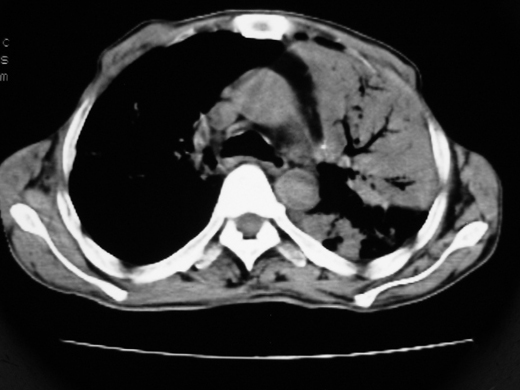

右肺多发片絮状结节状及时条索状影,左上肺实变,内可见虫蚀样空洞及支气管气象,左下肺片状及球形病灶,及胸腔积液征象,双肺病灶内多发钙化影,上纵隔向左侧移位,结合病史,考虑双肺继发型肺结核,左胸腔积液。

考虑双肺支气管内膜结核并左侧肺不张,左胸腔积液可能性大建议气管镜检查或抗结核治疗隔期复查

右肺多发片絮状、结节状及条索状影,左上肺实变,内可见虫蚀样空洞及支气管气象,左下肺片状及球形病灶,有胸腔积液征象,双肺病灶内多发钙化影,上纵隔向左侧移位,结合病史,考虑双肺继发型肺结核,左胸腔积液。 建议结合ppd检查或纤支镜检查!

双肺结核,左肺实变。左侧胸腔积液(部分包裹)。

右肺可见大片状、云絮状改变。右肺可见散在类圆形影,以外带多见。左肺实变,其内可见明显支气管走行影。纵隔淋巴结有增大,左侧胸腔积液。考虑1、肺结核;2、肺癌肺转移不除外;3、左侧胸腔积液。